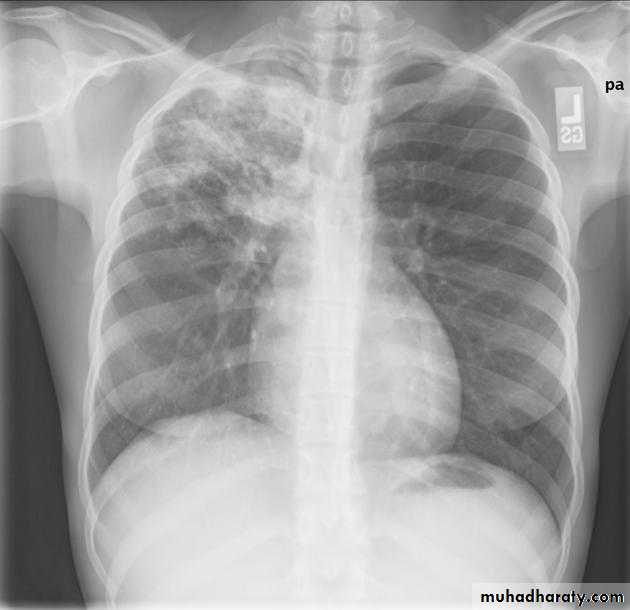

Lobular consolidation ( broncho pneumonia )

Very important to consider that pulmonary edema in normal sized heart have close similar appearance to broncho pneumonia

The important Golden Key differentiation is the cardiac size being enlarged in pulmonary edema .

36.lobuler consolidation (lobular pneumonia )37.discussion